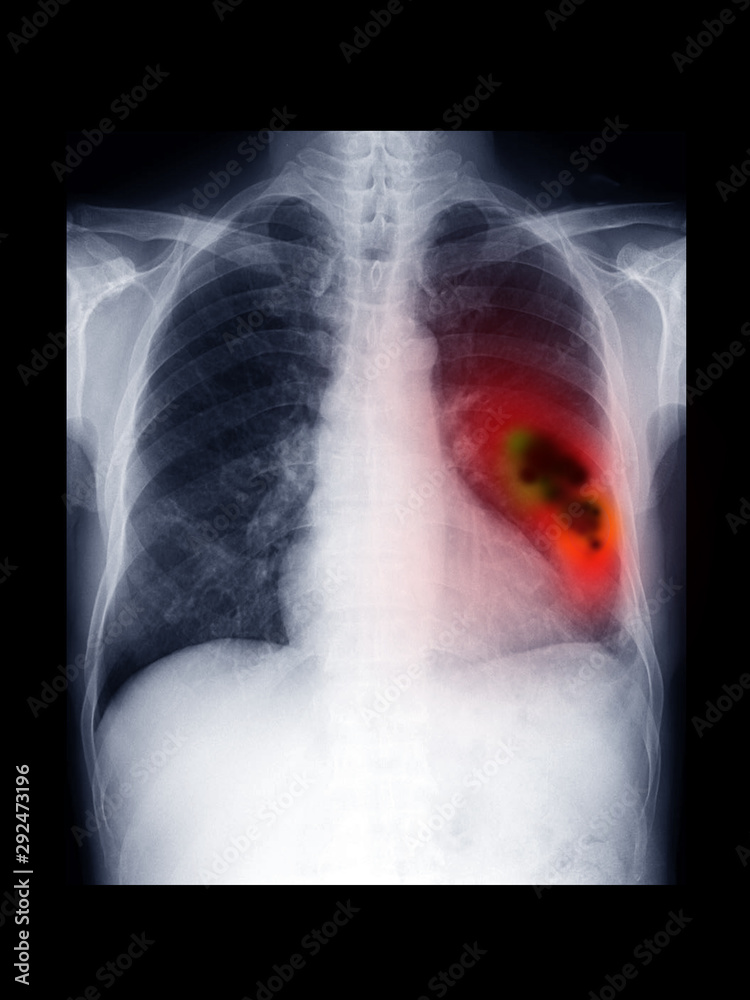

Colored chest xray showing primary lung cancer. The malignant tumour is the ballonshaped Chest X Ray Malignant Cancer To determine whether the likelihood of lung cancer is high or low, physicians usually look at three distinct characteristics of the nodule: Central tumors may result in hemoptysis and peripheral lesions with pleuritic chest pain. It has found extensive use in the past. Adenocarcinoma of the lung is the most common histologic type of lung cancer. Pneumonia, pleural effusion, wheeze,. Chest X Ray Malignant Cancer.

film xray chest radiograph (CXR) show lung mass. Lung cancer or carcinoma is malignant tumor Chest X Ray Malignant Cancer To determine whether the likelihood of lung cancer is high or low, physicians usually look at three distinct characteristics of the nodule: Central tumors may result in hemoptysis and peripheral lesions with pleuritic chest pain. The size of the spot, its shape and. Adenocarcinoma of the lung is the most common histologic type of lung cancer. Learn why and how. Chest X Ray Malignant Cancer.